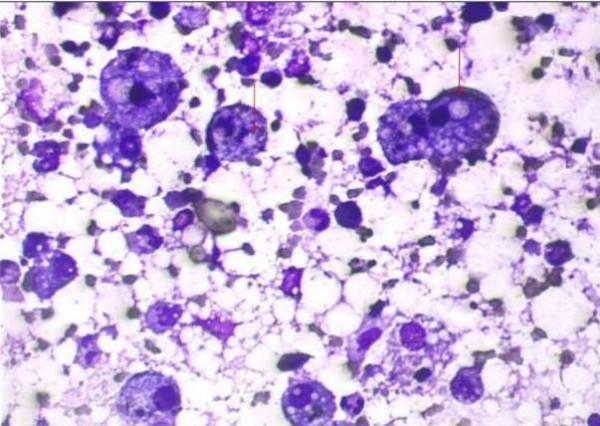

A 20-year old Indian farmer was referred to us with a diagnosis of non resolving community acquired pneumonia. Respiratory examination revealed signs of consolidation. Chest radiograph revealed findings suggestive of bilateral consolidation. Sputum and blood culture were sterile. He was treated with prolonged course of various antibiotics without any significant response. For evaluation of non resolving pneumonia fibreoptic bronchoscopy was done. Bronchoalveolar lavage fluid and biopsy from lung lesion showed lipid laden macrophages. Hence diagnosis of lipoid pneumonia was made. Patient was treated with course of corticosteroids with good response. Literature on this rare entity is discussed.

一名20岁的印度农民因诊断为难治性社区获得性肺炎被转诊至我院。呼吸检查发现实变体征。胸部X线片显示双侧实变的迹象。痰液和血培养均无菌。他接受了多种抗生素的长期治疗,但没有任何明显效果。为评估难治性肺炎,进行了纤维支气管镜检查。支气管肺泡灌洗液和肺病变活检显示含脂质巨噬细胞。因此,诊断为类脂性肺炎。患者接受了皮质类固醇治疗,效果良好。本文讨论了关于这个罕见疾病的文献。